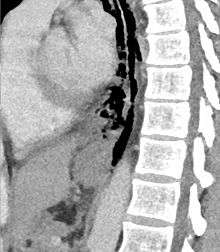

The diagnosis of Boerhaave's syndrome is suggested on the plain chest radiography and confirmed by chest CT scan. The initial plain chest radiograph is almost always abnormal in patients with Boerhaave's syndrome and usually reveals mediastinal or free peritoneal air as the initial radiologic manifestation. With cervical esophageal perforations, plain films of the neck show air in the soft tissues of the prevertebral space.

Hours to days later, pleural effusion(s) with or without pneumothorax, widened mediastinum, and subcutaneous emphysema are typically seen. CT scan may show esophageal wall edema and thickening, extraesophageal air, periesophageal fluid with or without gas bubbles, mediastinal widening, and air and fluid in the pleural spaces, retroperitoneum or lesser sac.